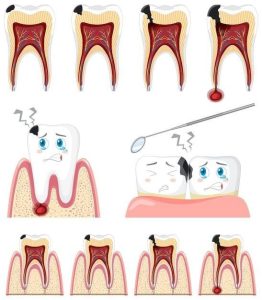

عصب کشی دندان (یا درمان ریشه)، یک درمان دندانپزشکی است که در آن دندانپزشک بافت عصبی آسیبدیده داخل دندان را که به دلیل پوسیدگی شدید، ضربه یا عفونت دچار التهاب یا آسیب شده است، پاک میکند. هدف این درمان، حفظ دندان و جلوگیری از کشیدن آن است.

پوسیدگی عمیق دندان: زمانی که پوسیدگی به عمق دندان برسد و به عصبها و بافتهای داخلی آسیب بزند، درمان ریشه ضروری میشود.

عفونت دندان: عفونت میتواند به دندان و بافتهای اطراف آن سرایت کند. در این صورت، عصب کشی برای جلوگیری از گسترش عفونت و حفظ سلامت دندان انجام میشود.

ضربه به دندان: آسیب فیزیکی به دندان مانند ضربه میتواند باعث آسیب به عصبهای دندان شود و درمان ریشه لازم گردد.